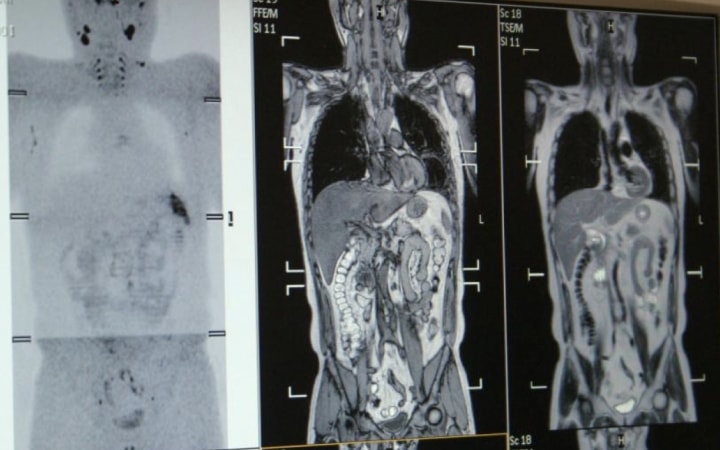

全身MRI(DWIBS)を通じて

「がんリスク検査」 陽性者*の不安を解消する